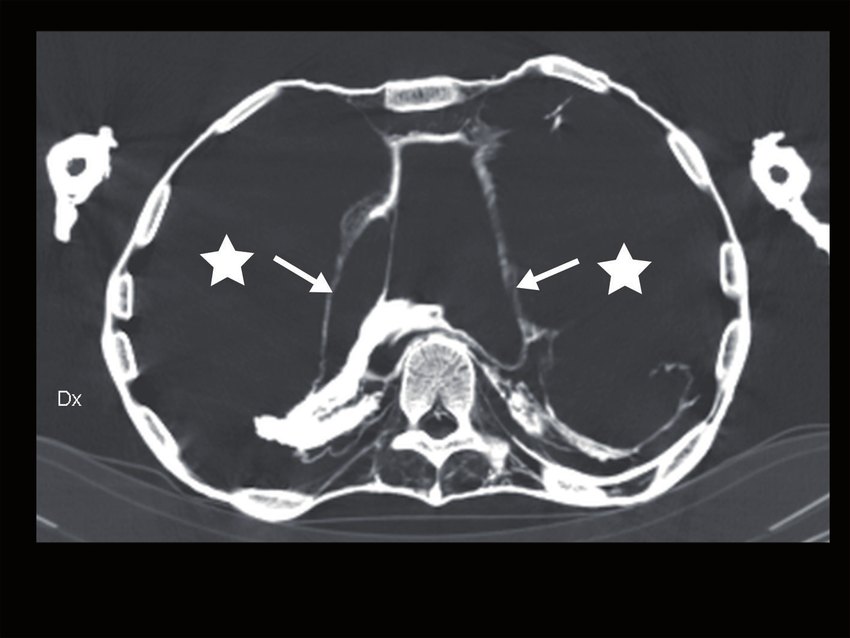

Già nel 2012 la TAC della mummia aveva svelato tagli sulla trachea e sull’esofago del re e nascosti dalle bende, avvalorando l’ipotesi che fosse stato sgozzato.

Qualche anno dopo uno studio pubblicato dalla rivista British Medical Journal, divulgato dal quotidiano egiziano Al-Ahram e ripreso poi dalle agenzie stampa di tutto il mondo ha infine provato che il faraone venne mutilato e ucciso da diversi assalitori armati e che dopo la morte subì una “chirurgia ricostruttiva” finalizzata a nascondere ferite e amputazioni.

Un’equipe di ricercatori incaricati degli studi sulle mummie reali – tra cui l’egittologo Zahi Hawass, l’esperto di genetica molecolare dell’Universita’ di Tubinga Carsten Pusch, i docenti di Radiologia e paleoradiologi dell’Università del Cairo Ashraf Selim e Sahar Selim ed il paleopatologo Albert Zink dell’Eurac di Bolzano, ha effettuato la scansione completa della mummia del faraone, conservata al Museo Egizio del Cairo ed ha scoperto che la gola di Ramses III è stata tagliata profondamente con un coltello affilato, che ha reciso la trachea, l’esofago e i grandi vasi sanguigni del collo fino a raggiungere l’osso sottostante e che al momento della morte gli venne anche amputata parte dell’alluce destro.

In un libro pubblicato nel 2016 (“Scansione dei faraoni: CT Imaging of the New Kingdom Royal Mummies”), Zahi Hawass e Sahar Saleem raccontano una fine drammatica, spiegando che il Faraone venne aggredito da più assassini che agirono contemporaneamente: la mutilazione al piede non guarita (per cui probabilmente perimortem) infatti, fa pensare ad un attacco frontale con un’ascia o una spada, in ogni caso con un’arma diversa da quella sottile ed appuntita che causò la profonda ferita alla gola, inferta ragionevolmente da un altro congiurato che si portò alle spalle della vittima.

La salma venne accuratamente ricomposta durante la mummificazione per restituire al Sovrano un corpo perfetto per l’Aldilà: gli imbalsamatori collocarono nel suo addome quattro figurine dei figli di Horus e dei materiali di riempimento per dare al cadavere un aspetto più verosimile, bendarono con spessi strati di lino la ferita al collo e vi inserirono un amuleto perche’ guarisse nell’aldila’ (un occhio di Horus) e sostituirono il dito mancante con una protesi post mortem realizzata in lino e ricoperta di spessi strati di resina.

Oggi e’ quasi certo che Pentawere morì impiccato, o per propria scelta, o perché costretto a farlo: il cadavere è stato sottoposto ad una TAC, che ha rivelato, oltre alla bocca irrigidita in una smorfia che potrebbe anche non essere significativa, il torace gonfio in modo anomalo e la pelle del collo recante segni probabilmente attribuibili a corde.